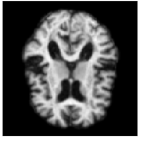

Figure 3: 4 time steps of a sample of the stochastic deformation process I0ϕt1subscript𝐼0superscriptsubscriptitalic-ϕ𝑡1I_{0}\circ\phi_{t}^{-1} at t=0, 0.25, 0.5, 1𝑡00.250.51t=0,\,0.25,\,0.5,\,1.

By drawing sample paths of the stochastic flow ϕt1superscriptsubscriptitalic-ϕ𝑡1\phi_{t}^{-1}, we obtain samples of deformed images under the model. Sample images at t=1𝑡1t=1 are shown in Fig. 2, together with a plot of the generated image variation, and the noise fields used to simulate the sample data. Fig. 3 shows 4 time points from a sample path of the stochastic process I0ϕt1subscript𝐼0superscriptsubscriptitalic-ϕ𝑡1I_{0}\circ\phi_{t}^{-1} for t=0, 0.25, 0.5, 1𝑡00.250.51t=0,\,0.25,\,0.5,\,1.